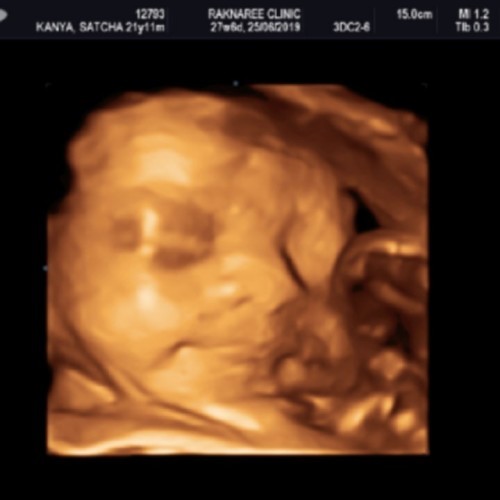

บ้านนี้กำหนดคลอด 22มิถุนาค่ะ ยังไม่รู้เพศเลย น้องหนีบไว้? น้องดิ้นเก่งมาก แม่ท่านไหนกำหนดคลอดมิถุนาบ้าง รู้เพศลูกกันรึยังค่ะ แม่อยากได้ผู้หญิงมากเลย